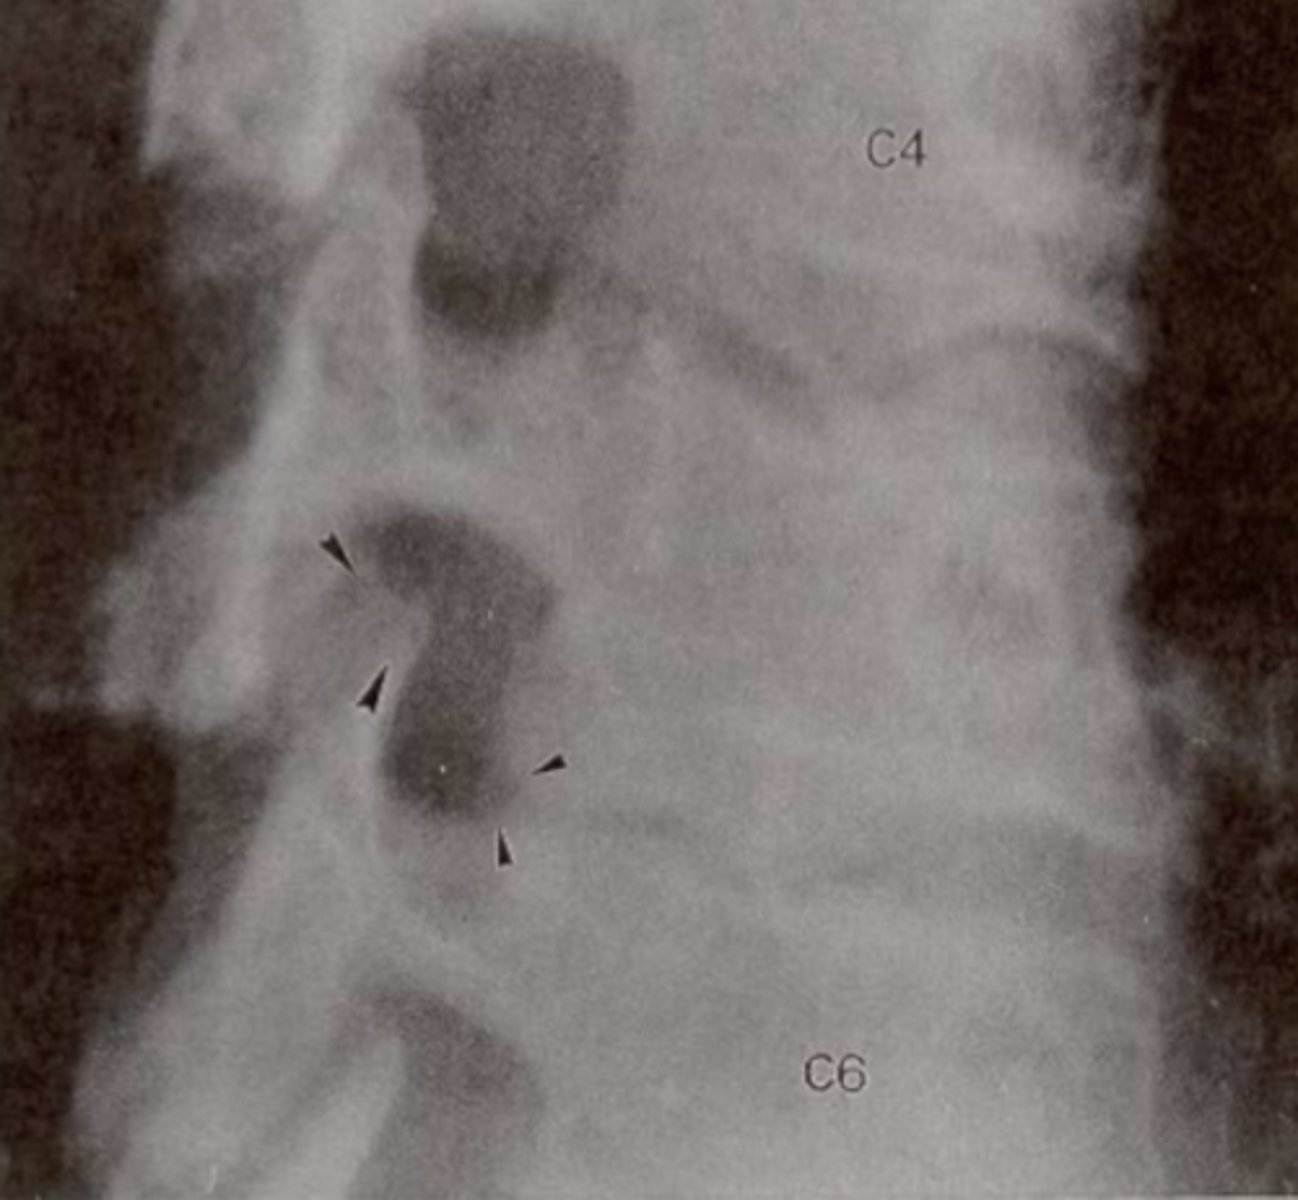

Oblique Cspine

What view is this?

Stenosis

What is the issue?